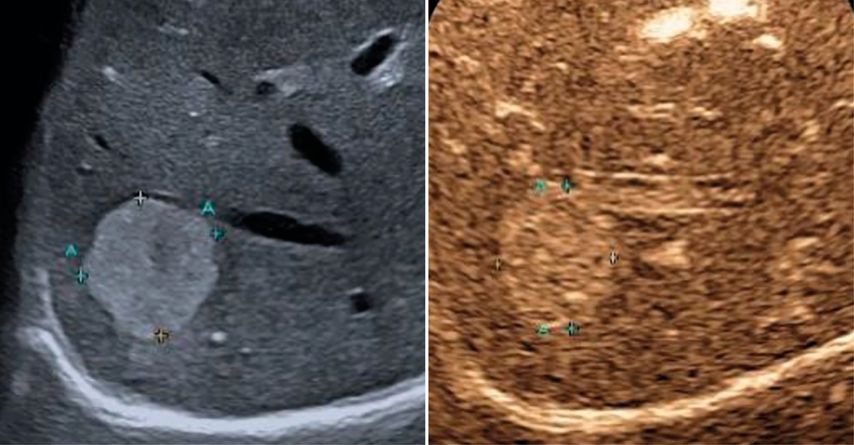

Trotz der hohen Aussagekraft moderner Ultraschallgeräte im B-Mode kann derzeit – mit Ausnahme des Screenings auf hepatozelluläre Karzinome bei chronischen Lebererkrankungen – kein generelles Leberscreening empfohlen werden.5 Die Mehrzahl fokaler Leberläsionen ist benigne, darunter fokale Steatosen, Zysten, Hämangiome oder fokale noduläre Hyperplasien (Abb.3). Maligne Raumforderungen sind in populationsbasierten Studien selten.6

Abb. 3: Darstellung einer fokalen nodulären Hyperplasie (FNH) in der arteriellen Frühphase nach Gabe von 1,2ml SonoVue® mittels CEUS (links) und in der mikrovaskulären Bildgebung (Canon®-superb „Microvascular imaging“-Modus), wo die Radspeichenstruktur besser zur Darstellung kommt